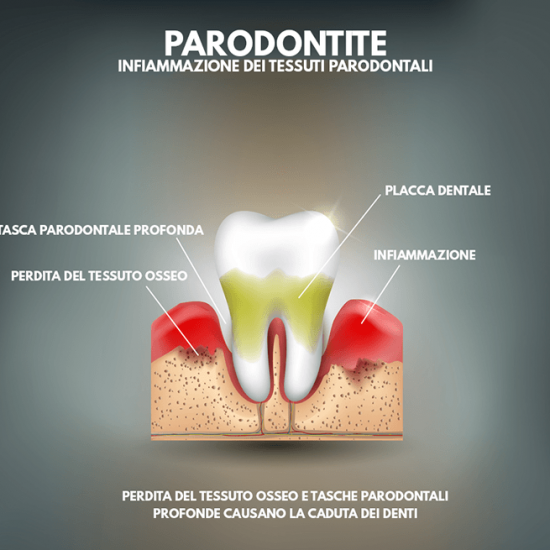

Patologie come la Parodontite, oggi più propriamente definita Malattia Parodontale, sono spesso asintomatiche fino al palesarsi di conseguenze irreversibili.

Dovete sapere che è possibile distinguere all’interno del cavo orale due grandi famiglie di batteri: i primi responsabili di problemi agli elementi dentali (carie), i secondi responsabili dei problemi gengivali (paradontite).

Non aspettate evidenze irreversibili, quali la mobilità dentale o la formazione di tasche gengivali purulente, rivolgetevi a Noi prima, passate per un controllo. E’ Gratis.